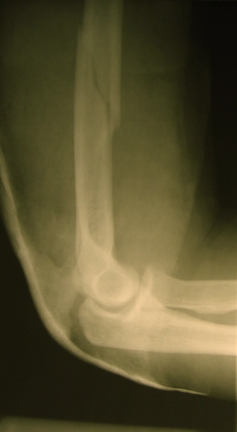

что  не  получилось  и  берем  на  операцию. Теперь непосредственно по

больному.   Лечим   функциональной   повязкой,   добились   вот   чего

(приложение).  Будем  признательны  за  дальнейший  комментарий  - мое

мнение, что можно продолжить без операции.

Вложение не в текстовом формате было извлечено…

Имя     : Боковой.JPG

Тип     : image/jpeg

Размер  : 44426 байтов

Описание: отсутствует

Url     : http://weborto.net:8080/pipermail/ortho/attachments/20100223/f10e997d/attachment-0007.jpeg